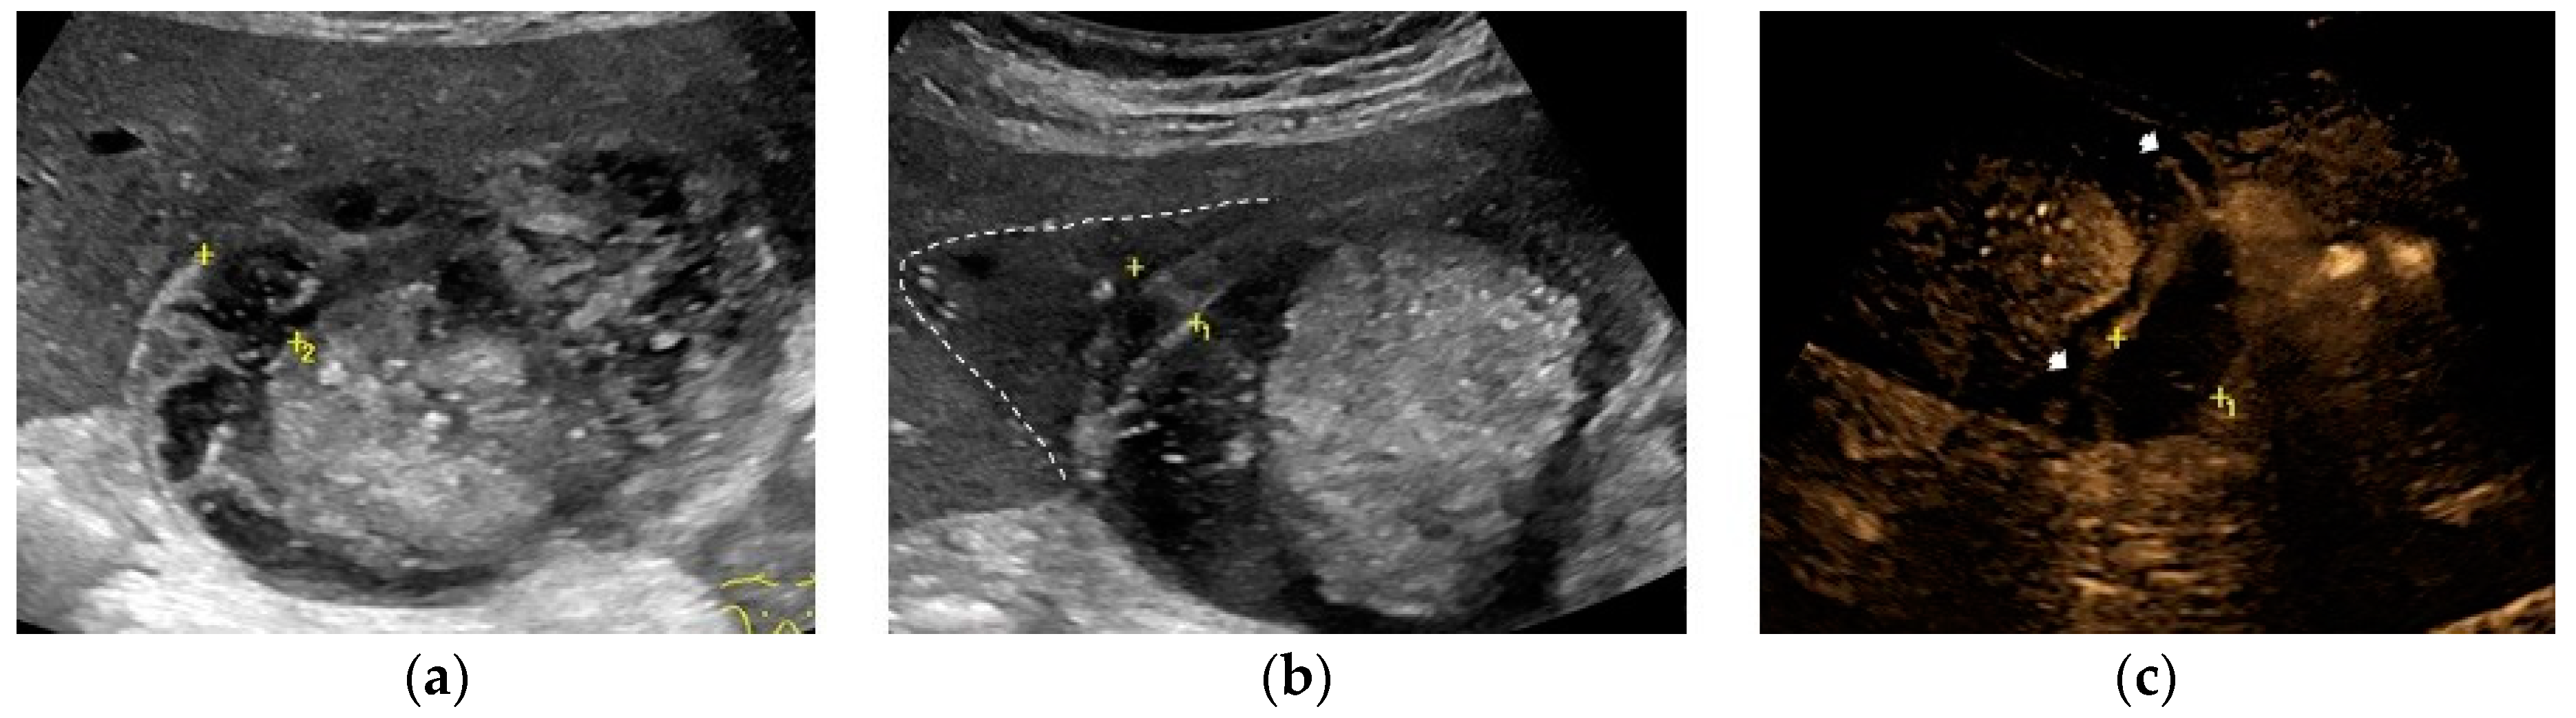

The most common sonographic finding in GC is an irregular gallbladder wall thickening,[49,50] characterized by multiple striations with alternating hypoechoic or hyperechoic bands (Figure 2). [27] This sonographic pattern is due to the presence of intramural hemorrhage or micro-abscesses. [3,44] Intraluminal membranes, formed by strands of fibrinous exudate and desquamated or “denuded” mucosa, are considered a more specific finding in GC, although less common (Figure 3).[3,44,49,50]

At US examination, the hallmark for the diagnosis of gallbladder perforation consists in the “hole sign”, present in 45-70% of cases [27] and characterized by a full-thickness defect of the gallbladder wall (Figure 3 and Figure 4).[44,50,57,58] Defects in the gallbladder wall are usually focal and small. However, in case of perforation secondary to infectious necrosis, a large defect may be observed. [59] The full-thickness disruption of the gallbladder wall can be further highlighted by CEUS examination. [20,37,58,60]

In case of a subacute process, gallbladder perforation generally results in pericholecystic abscess or, rarely, in a liver abscess (Figure 3).[49]